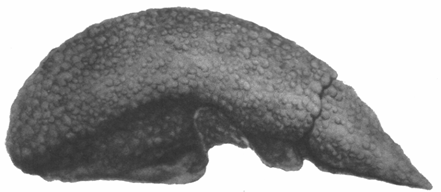

Рассеянные очаги некроза печеночных клеток и усиленная пролиферация внутридольковых мезенхимальных клеток обусловливают выраженное в большей или меньшей степени нарушение балочного строения и диссоциацию печеночных клеток или комплексов их (рис. 1 и отд. табл., рис. 3).

Рис. 1. Острая форма болезни Боткина (мальчик 4—6 месяцев). Рассеянные некрозы печеночных клеток. В просветах капилляров скопление макрофагальных клеток с явлениями фагоцитоза.